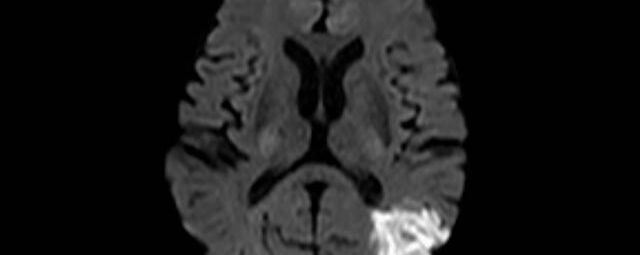

Die multiparametrische MRT (mpMRT) der Prostata ist ein modernes, strahlungsfreies Verfahren zur Früherkennung und Abklärung von Prostatakrebs. Sie kombiniert verschiedene MRT-Techniken (T2, DWI, DCE) und ermöglicht eine präzise Darstellung verdächtiger Areale. Laut aktuellen Leitlinien der Deutschen Röntgengesellschaft und Deutschen Gesellschaft für Urologie ist sie der empfohlene Standard bei erhöhtem PSA-Werten, vor Biopsien oder bei unklaren Vorbefunden.

- Diffusionswichtung

- Perfusionswichtung

- Suszeptibilitätswichtung

- MR-Spektroskopie

Diese Verfahren werden bei verschiedenen Fragestellungen in verschiedenen Körperregionen in die Messprotokolle sinnvoll eingefügt. Teilweise können dadurch Differenzierungenverschiedener krankhafter Prozesse verbessert werden.